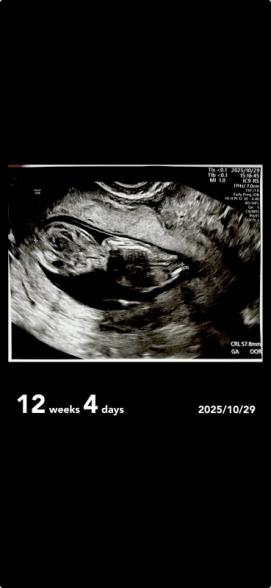

12週エコー

先日エコーを見ていたところ気になったことがあったので質問したいです。

頭の脳みそは12週目だったらみんなこんな感じなんですかね?

他の人のエコーとか見ていたら少し違う気がして気になりました。(一枚目)